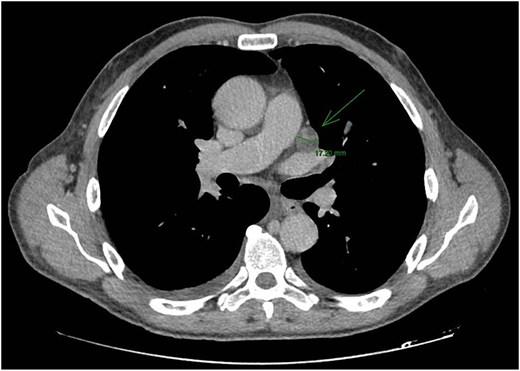

CT staging of the chest and pelvis showed the presence of subaortic, peri-esophageal, and hilar necrotic lymph node enlargement on the left, suggestive of secondary implants (Fig. 2). Then, a biopsy of the largest liver lesion showed a metastasis of OPSCC. Individual cells were large and pleomorphic with moderate amount of eosinophilic cytoplasm and high nuclear-cytoplasmic ratio. Nuclei were large, pleomorphic, and hyperchromatic with prominent nuclei (Fig. 3). Immunohistochemically, the tumor cells were cytokeratin 5/6(+) (Fig. 4a) and p40 (+) (Fig. 4b). The liver biopsy was compared with the primary OPSCC histological specimen. Morphological features and immunohistochemical profiles were consistent with metastatic oropharyngeal squamous cell carcinoma.

CT staging of the chest and pelvis showed the presence of subaortic, peri-esophageal, and hilar necrotic lymph node enlargement on the left, suggestive of secondary implants.